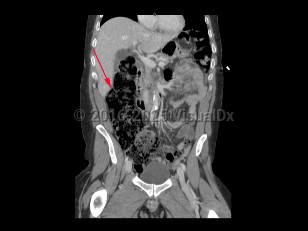

A large bowel obstruction (LBO) occurs when intraluminal contents fail to pass through the large intestine. This results in dilation of the proximal large bowel, with fluid accumulation, gas production, increased intraluminal pressure, and bacterial overgrowth. Bacterial translocation can then lead to bacteremia and sepsis.

LBOs may be partial or complete. A simple LBO is characterized by a single point of obstruction. A closed-loop obstruction is characterized by occlusion of the bowel at 2 points and has the highest risk of ischemia due to occlusion of the blood supply. A classic example of this is sigmoid volvulus. A competent ileocecal valve may also contribute to closed loop obstructions as the large bowel cannot decompress proximally.

Patients present with severe abdominal distension and inability to pass stool or flatus. Abdominal pain due to LBO is typically less severe and more gradual in onset compared to SBO. However, patients with LBO typically have more severe distension compared to SBO, as well as nausea and vomiting.

Obstruction leads to increased colonic dilation, eventually leading to necrosis and perforation of the bowel. Patients with bowel ischemia or perforation usually have more severe presentations, often with signs of peritonitis, sepsis, and hemodynamic instability.